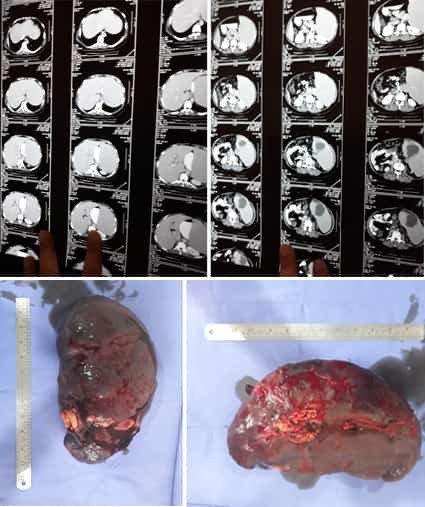

A Young lady who was a small kid...when her mother was operated for a Complex Gastrointestinal condition almost 14 years back by Dr Suddhasattwa Sen suddenly came in with severe blood loss from Gastrointestinal tract with a loss of almost 2 to 3 litres of blood with Shock with fainting . Further stabilisation was done and then extensive investigation revealed not only Piles and GI Ulcers but also SRUS Bleeding ulcers in rectum. A condition called Solitary Rectal Ulcer Syndrome ( a complex and difficult to cure anorectal problem ) . Her hemoglobin dropped to below 7 gm% She finally underwent surgery after 5 days and left home after 2 days post op without any further bleed or problems .